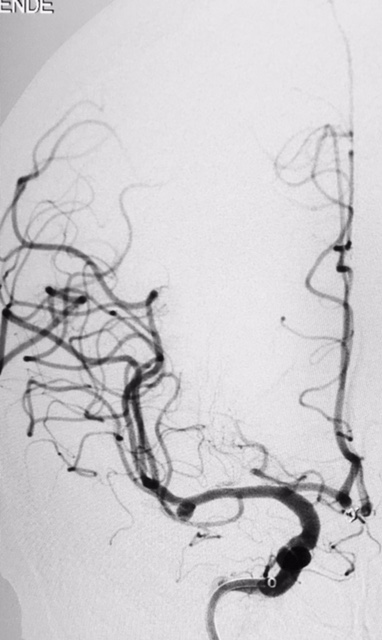

Tratamento de aneurisma cerebral com auxílio de balão duplo lumém e neurostent LEO